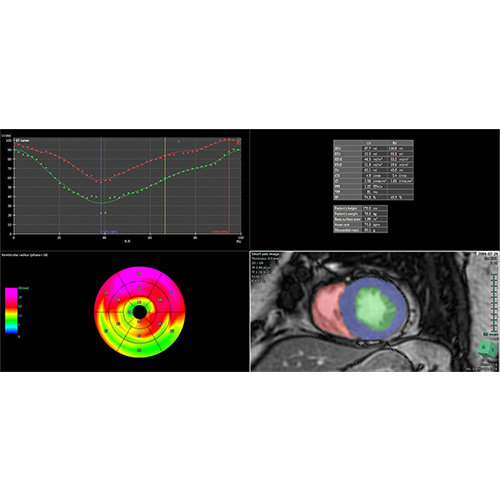

ANYTHINK 经导管主动脉瓣膜置换术分析系统